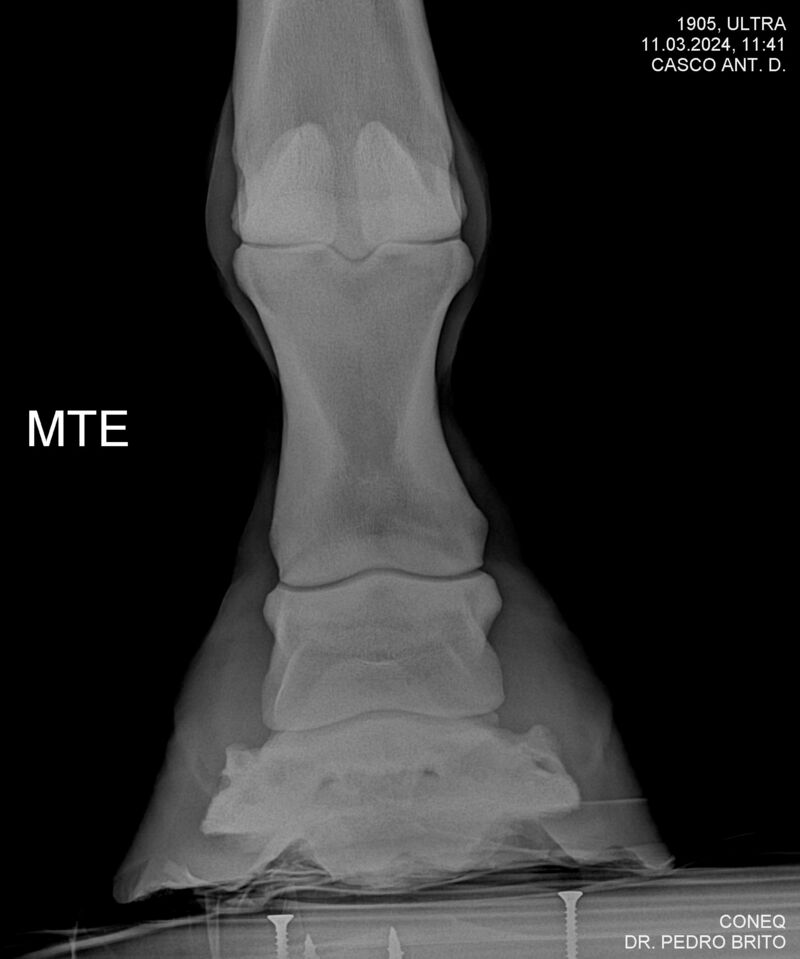

ULTRA DO CACH

Raça: BRASILEIRO DE HIPISMO

Sexo: CASTRADO - CASTRADO

Nascimento: 22/11/2020

Altura Aproximada: 1,67

Pel.: CASTANHO

Registro: 25966-BH

Vend.: HARAS CACHOEIRINHA

Local : PIRASSUNUNGA/SP